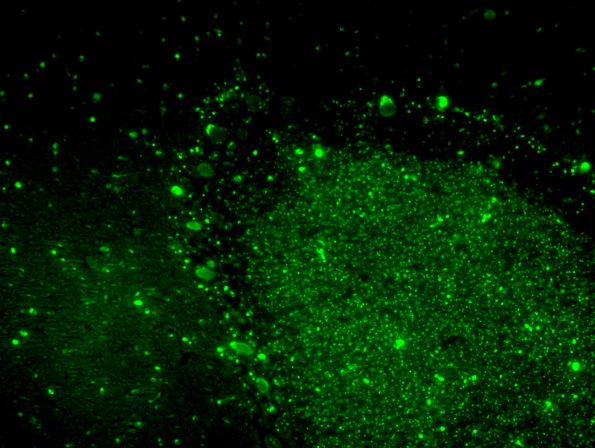

Neuronal Ceroid Lipofuscinosis (NCL)

2H6 NCL (Case 2) L14 Autofluorescence 6C